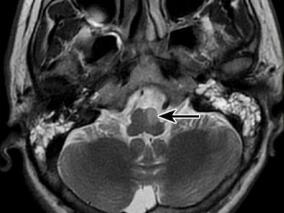

1小时条评论Ondinersquo;s curse综合征是中枢性睡眠呼吸暂停综合征(central sleep apnea syndrome)的一种特殊类型,主要表现为睡眠状态时出现的二氧化碳潴留、低氧血症及呼吸暂停[1]。该命名来源于德国的一个古老传说,女神Ondine的惩罚会在夜间降临到那些犯了错误的人身上。 ...